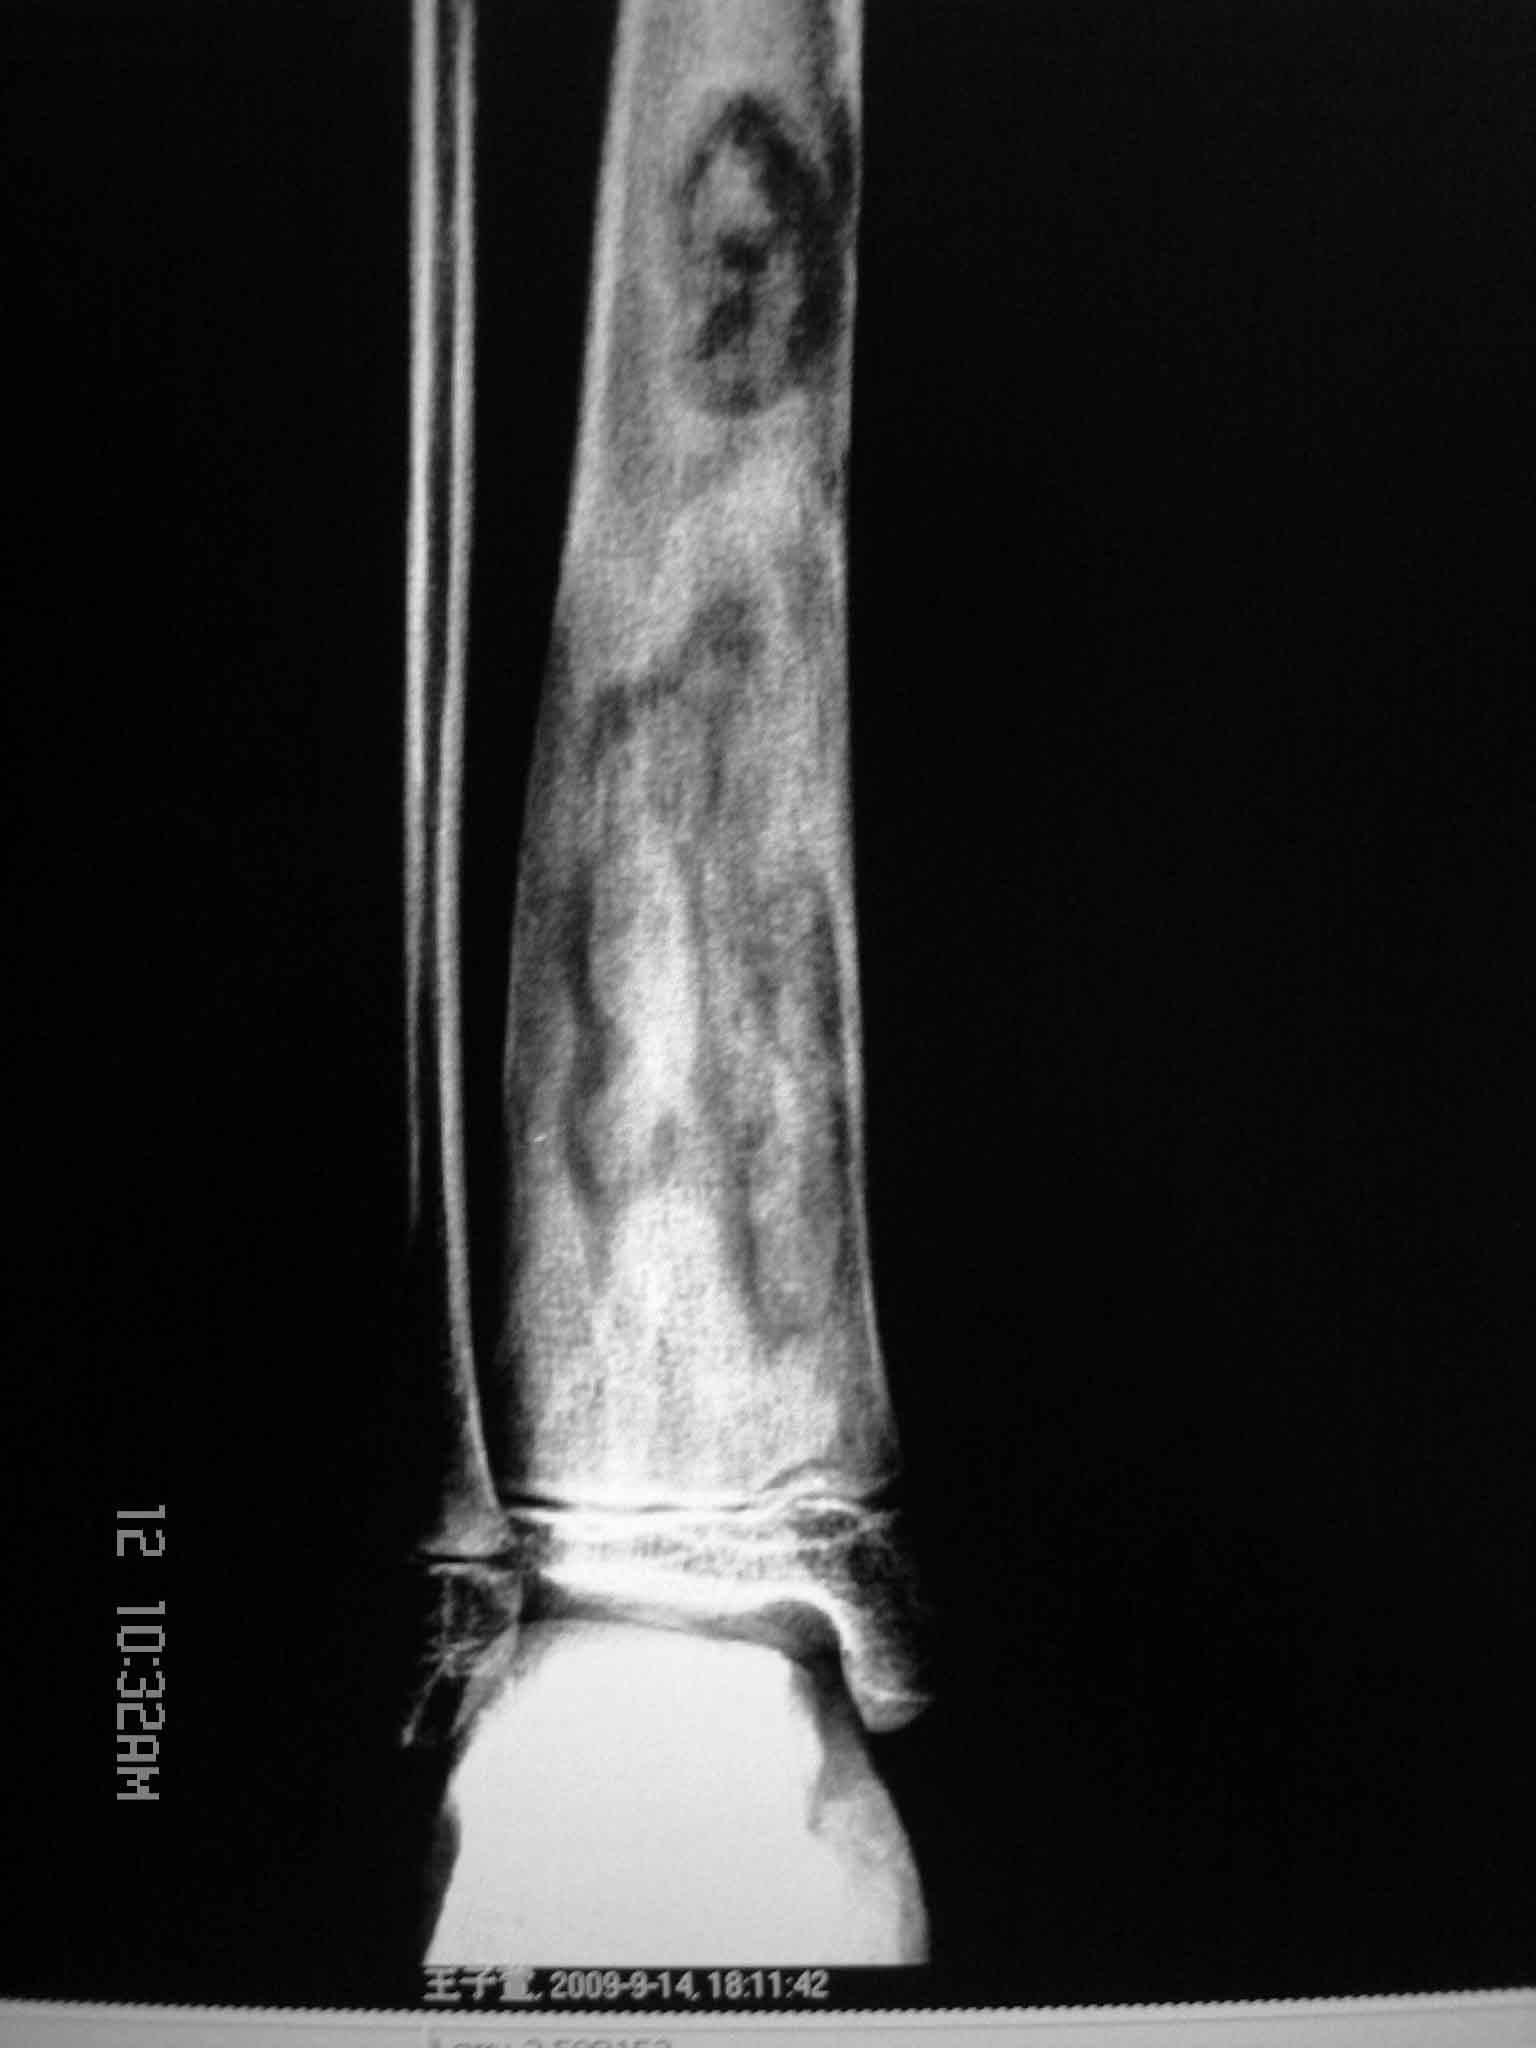

女孩10岁,右小腿痛3年。是骨纤吗?

右胫骨下段增粗,内见多个长条状、类圆形骨质破坏区,边缘增生、硬化,内可见高密度坏骨块。不支持骨纤,考虑慢性化脓性骨髓炎。

临床病史,症状等对诊断帮助很大。支持慢性骨髓炎。骨纤密度还是相对均一的,4种形态:磨玻璃样,丝瓜瓤样,虫蚀样,囊状膨胀样改变。再者骨纤的症状相对轻微。

右胫骨下段增粗,内见多个长条状、类圆形骨质破坏区,边缘增生、硬化,内可见高密度坏骨块。不支持骨纤,考虑慢性化脓性骨髓炎。支持